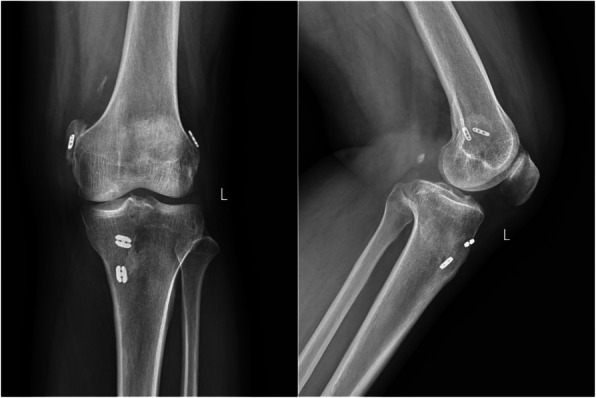

Septic arthritis or adult-onset still's disease: analyzing the causes of recurrent fever after arthroscopic combined anterior cruciate ligament and posterior cruciate ligament reconstruction: a case report.